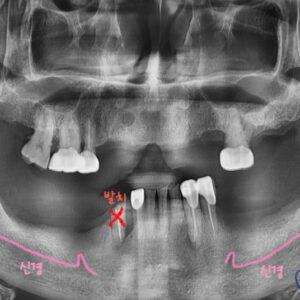

남아있는 치아 모두 발치 후

치아를 모두 발치 후,

치료 비용의 부담,

치조골의 흡수,

등의 이유로 전악 임플란트를 할 수 없는 경우가 있습니다.

그런 경우, 위 케이스와 같이 소수의 임플란트와 부분틀니를 이용하여

치아 수복을 할 수 있습니다.

물론, 기존 자신의 치아나

전체 임플란트에 비해서는 약간 불편할 수 있으나,

전체 틀니에 비해서는

훨씬 편안하게 사용이 가능합니다.